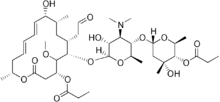

| Formula | C41H67NO15 |

| Melting point | 155 to 156 °C (311 to 313 °F) |

| Solubility in water | Soluble in acidic/low pH water; Very soluble in methanol, chloroform, ethyl acetate, benzene, ethyl ether; Almost completely in ethanol(>95.5) mg/mL (20 °C) |

Midecamycin is a macrolide antibiotic[1] that is synthesized from Streptomyces mycarofaciens.[2]